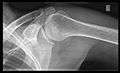

- Transaxillary projection

The arm should be abducted 80 to 100 degrees. This method reveals:[19]

- The horizontal alignment of the humerus head in respect to the socket, and the lateral clavicle in respect to the acromion.

- Lesions of the anterior and posterior socket border or of the tuberculum minus.

- The eventual non-closure of the acromial apophysis.

- The coraco-humeral interval

Transaxillary conventional radiography